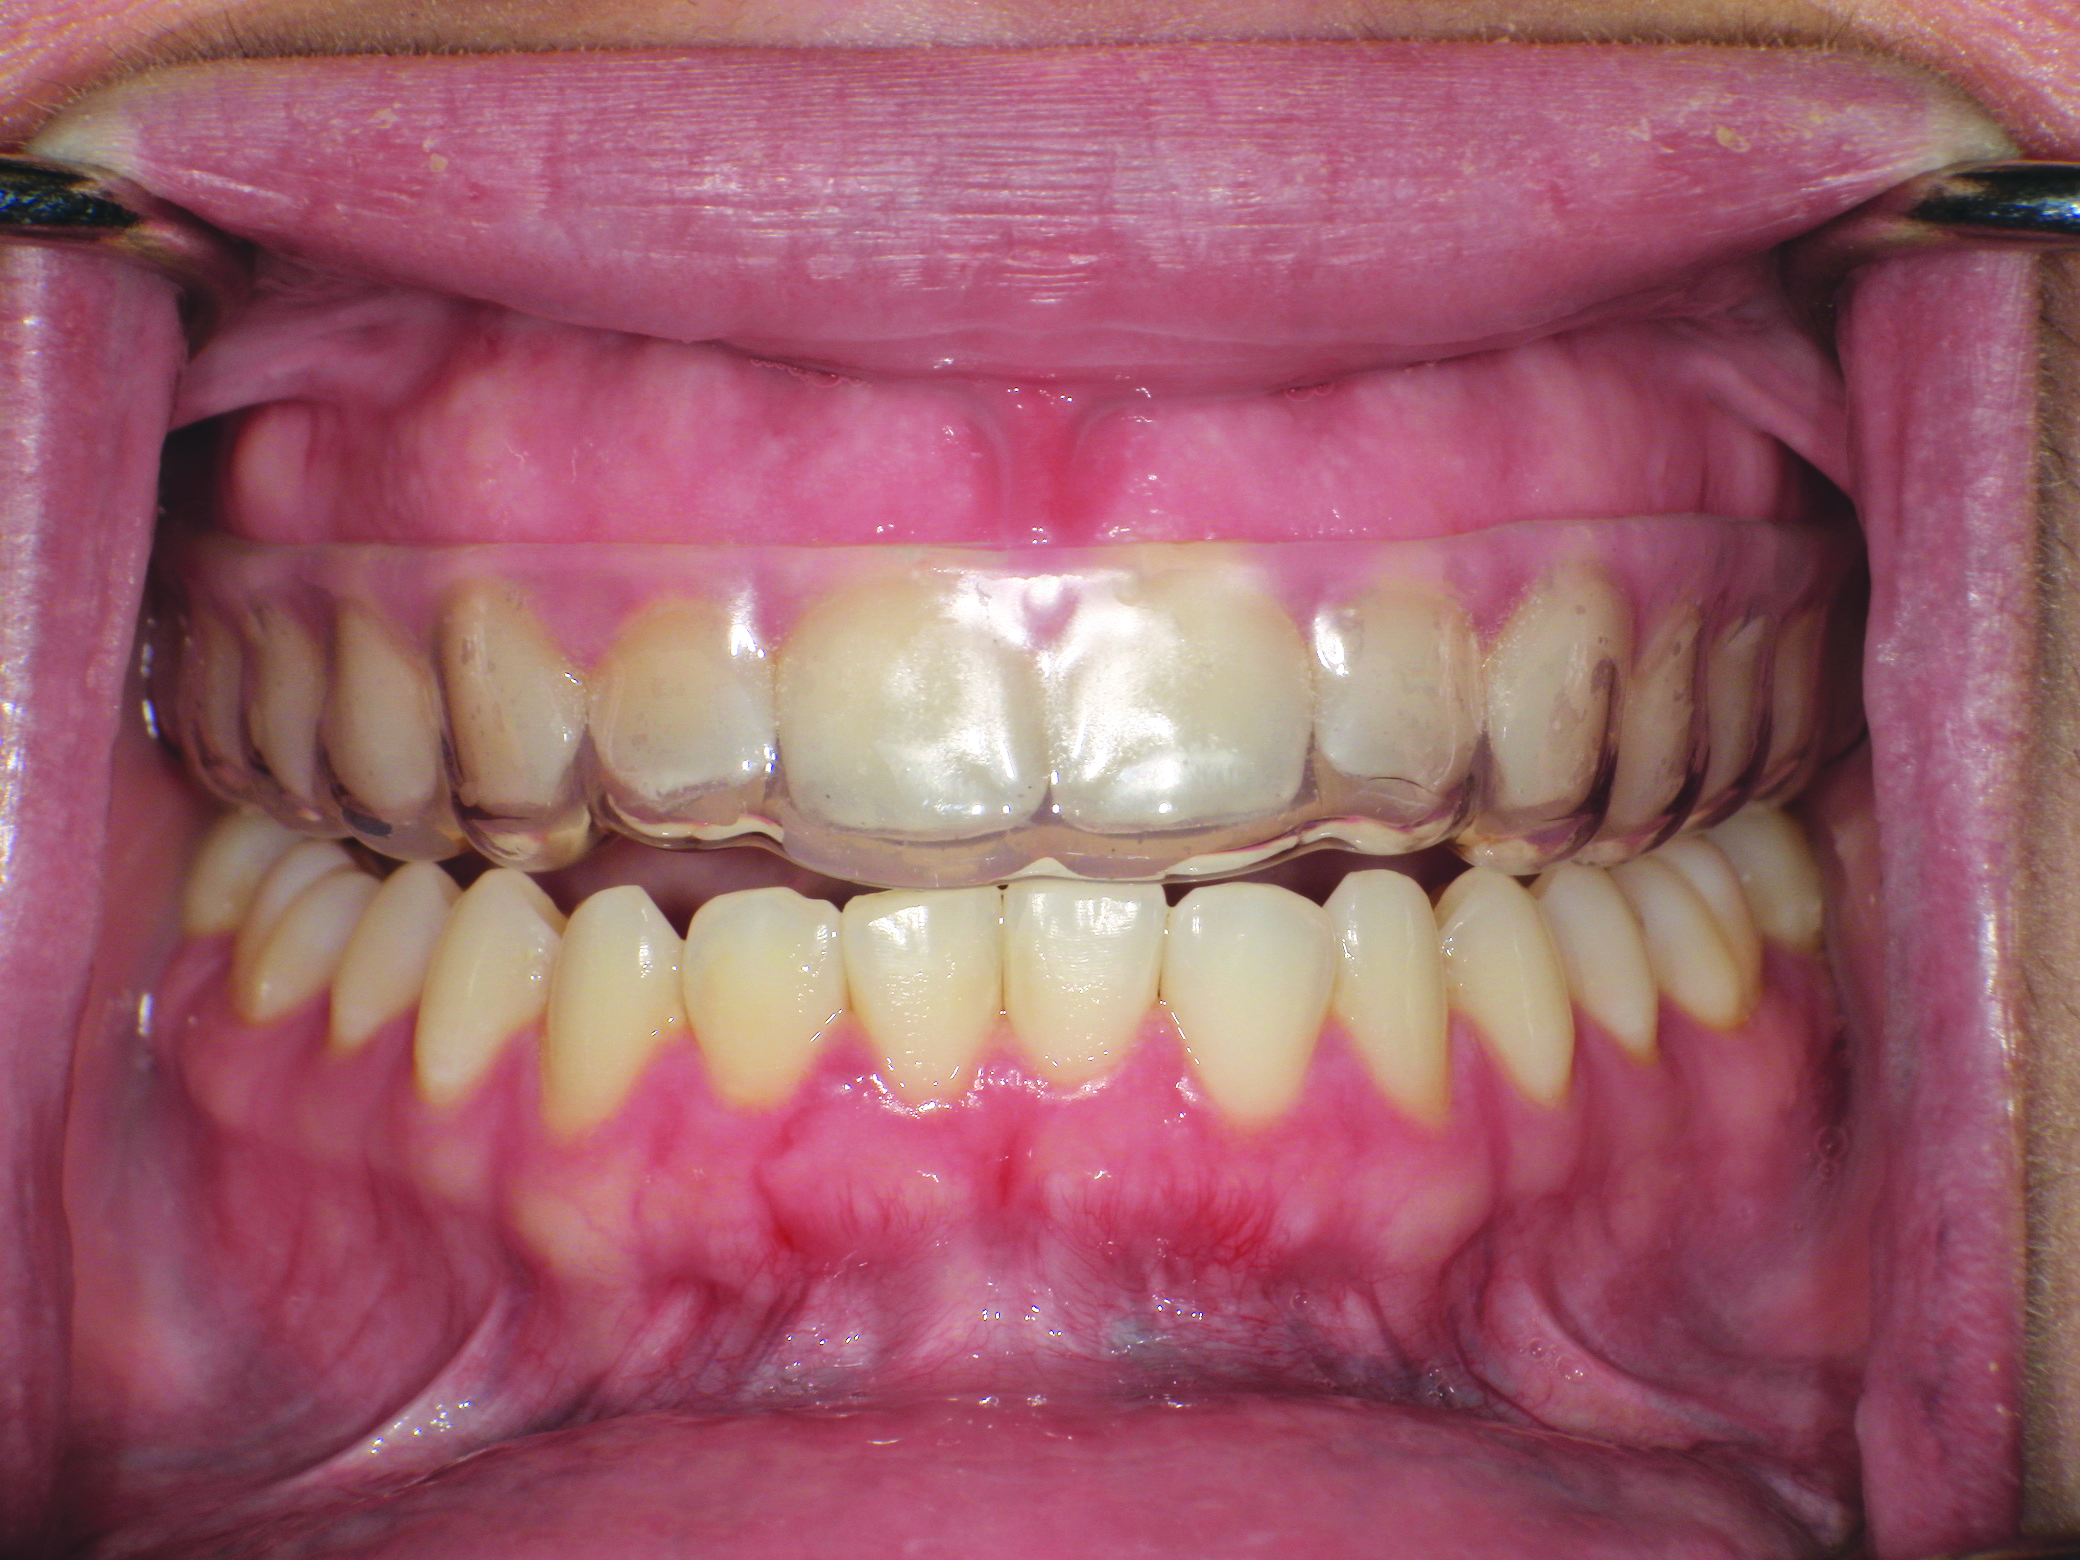

(3.) Intraoral facial and occlusal views, respectively, of the completed boil-and-bite sports mouth guard.

Figure 3

(4.) Intraoral facial and occlusal views, respectively, of the completed boil-and-bite sports mouth guard.

Figure 4

It should be noted that variation in the elastic modulus of the overlying laminate can significantly affect the device’s ability to prevent hard- and soft-tissue damage. Control over the thickness of in-office fabricated sports mouth guards can be obtained using combinations of inner and outer laminated layers.1 The finished product should have bilateral interocclusal contacts (Figure 7), cover all labial and lingual maxillary tooth surfaces, and have an open palate (Figure 8).